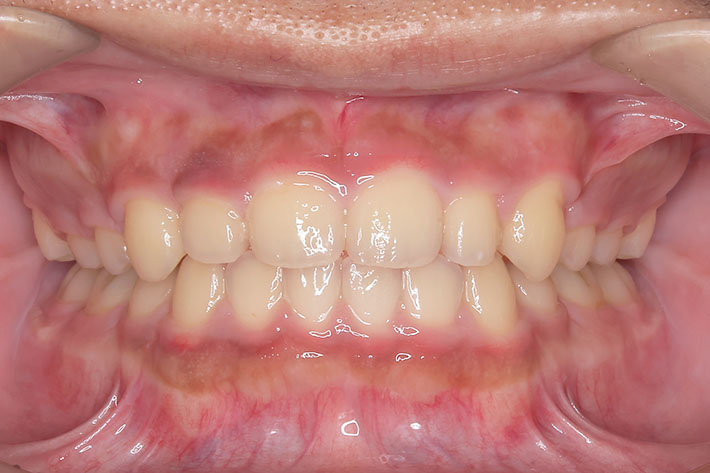

右上の前歯が生えてこない事を気にされ来院されました。 レントゲン写真から、上顎正中に過剰歯が埋伏していることが原因でしたので、抜歯して経過観察。 遅れて、無事に生えてきました。 もし、自然に生えてこない場合は、開窓して、引っぱり出します。(廷出) 状態により、引っぱり出せない場合もあります。 将来的にスペース不足により、上下顎前臼歯部に重度の叢生(がたつき)が予測できますので、がたつきを減らすために、小児矯正で側方拡大を行いました。 小児矯正で側方拡大を行ってもスペースが足りない場合(著しくスペース不足の場合)は、がたつき(叢生、八重歯)が残ります。 残ったがたつき(叢生)は、本格矯正ですべて生え変わった中学生から治せば問題ありません。 来院間隔が平均で1.5カ月でしたので半年ほど治療期間が長いです。